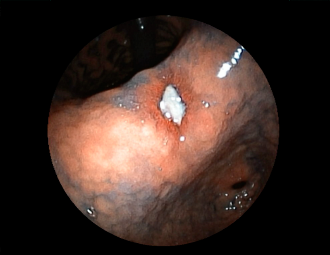

症例5:胃腺腫(84才女性)

胃角部に、大きさ10mm強のなだらかな粘膜隆起を認める。生検:Tubularadenoma with moderate atypia.Group 3。経過観察中。

通常画像